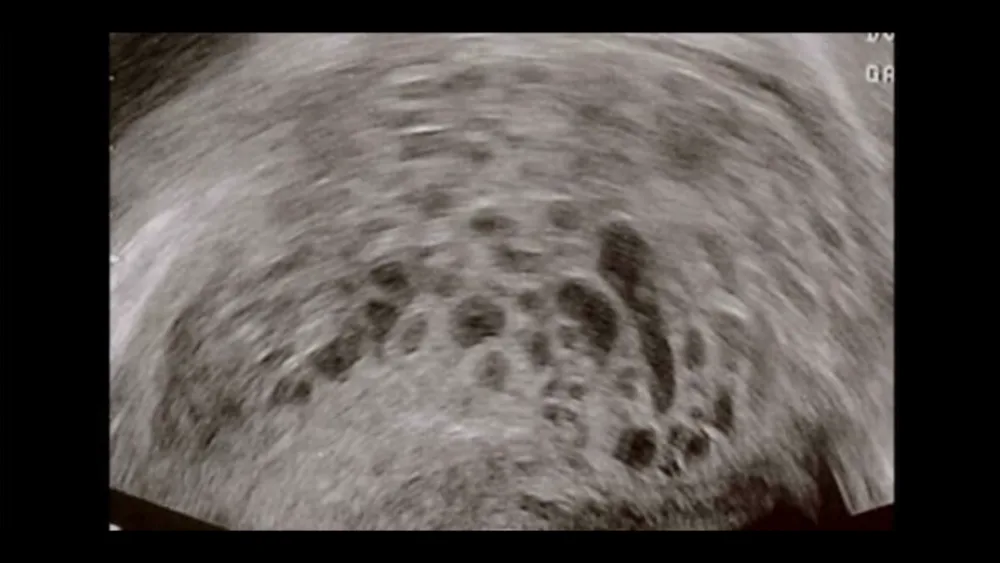

ครรภ์ไข่ปลาอุก (Molar Pregnancy/Hydatidiform Mole) คือ ภาวะการตั้งครรภ์ที่ไม่สมบูรณ์ โดยตัวอ่อนของทารกและรกไม่เจริญขึ้นมาตามปกติ เนื้อเยื่อของตัวอ่อนกลายเป็นเนื้องอกชนิดไม่ร้ายแรงในมดลูกแทน โดยทั่วไป รกจะช่วยลำเลียงสารอาหารไปเลี้ยงทารกในครรภ์ รวมทั้งกำจัดของเสียออกไป หากเซลล์ที่สร้างรกทำงานผิดปกติหลังจากที่ไข่ปฏิสนธิกับอสุจิแล้ว จะทำให้เกิดถุงน้ำรังไข่หรือซีสต์ ซึ่งมีลักษณะคล้ายพวงองุ่นสีขาวหรือไข่ปลา เซลล์ดังกล่าวจะเจริญภายในมดลูกอย่างรวดเร็วแทนการเจริญเป็นทารกโดยมีชื่อเรียกว่าครรภ์ไข่ปลาอุก แม้ครรภ์ไข่ปลาอุกจะเป็นเนื้องอกชนิดไม่ร้ายแรง แต่ถือเป็นภาวะก่อนเป็นมะเร็งของโรคมะเร็งไข่ปลาอุกหรือมะเร็งเนื้อรก (Gestational Trophoblastic Disease)